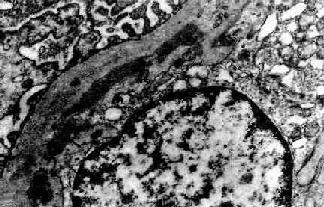

图12-15 膜性增生性肾小球肾炎 Ⅰ型

肾小球毛细血管基底膜内侧,内皮细胞下电子致密沉积物,部分上皮细胞足突消失